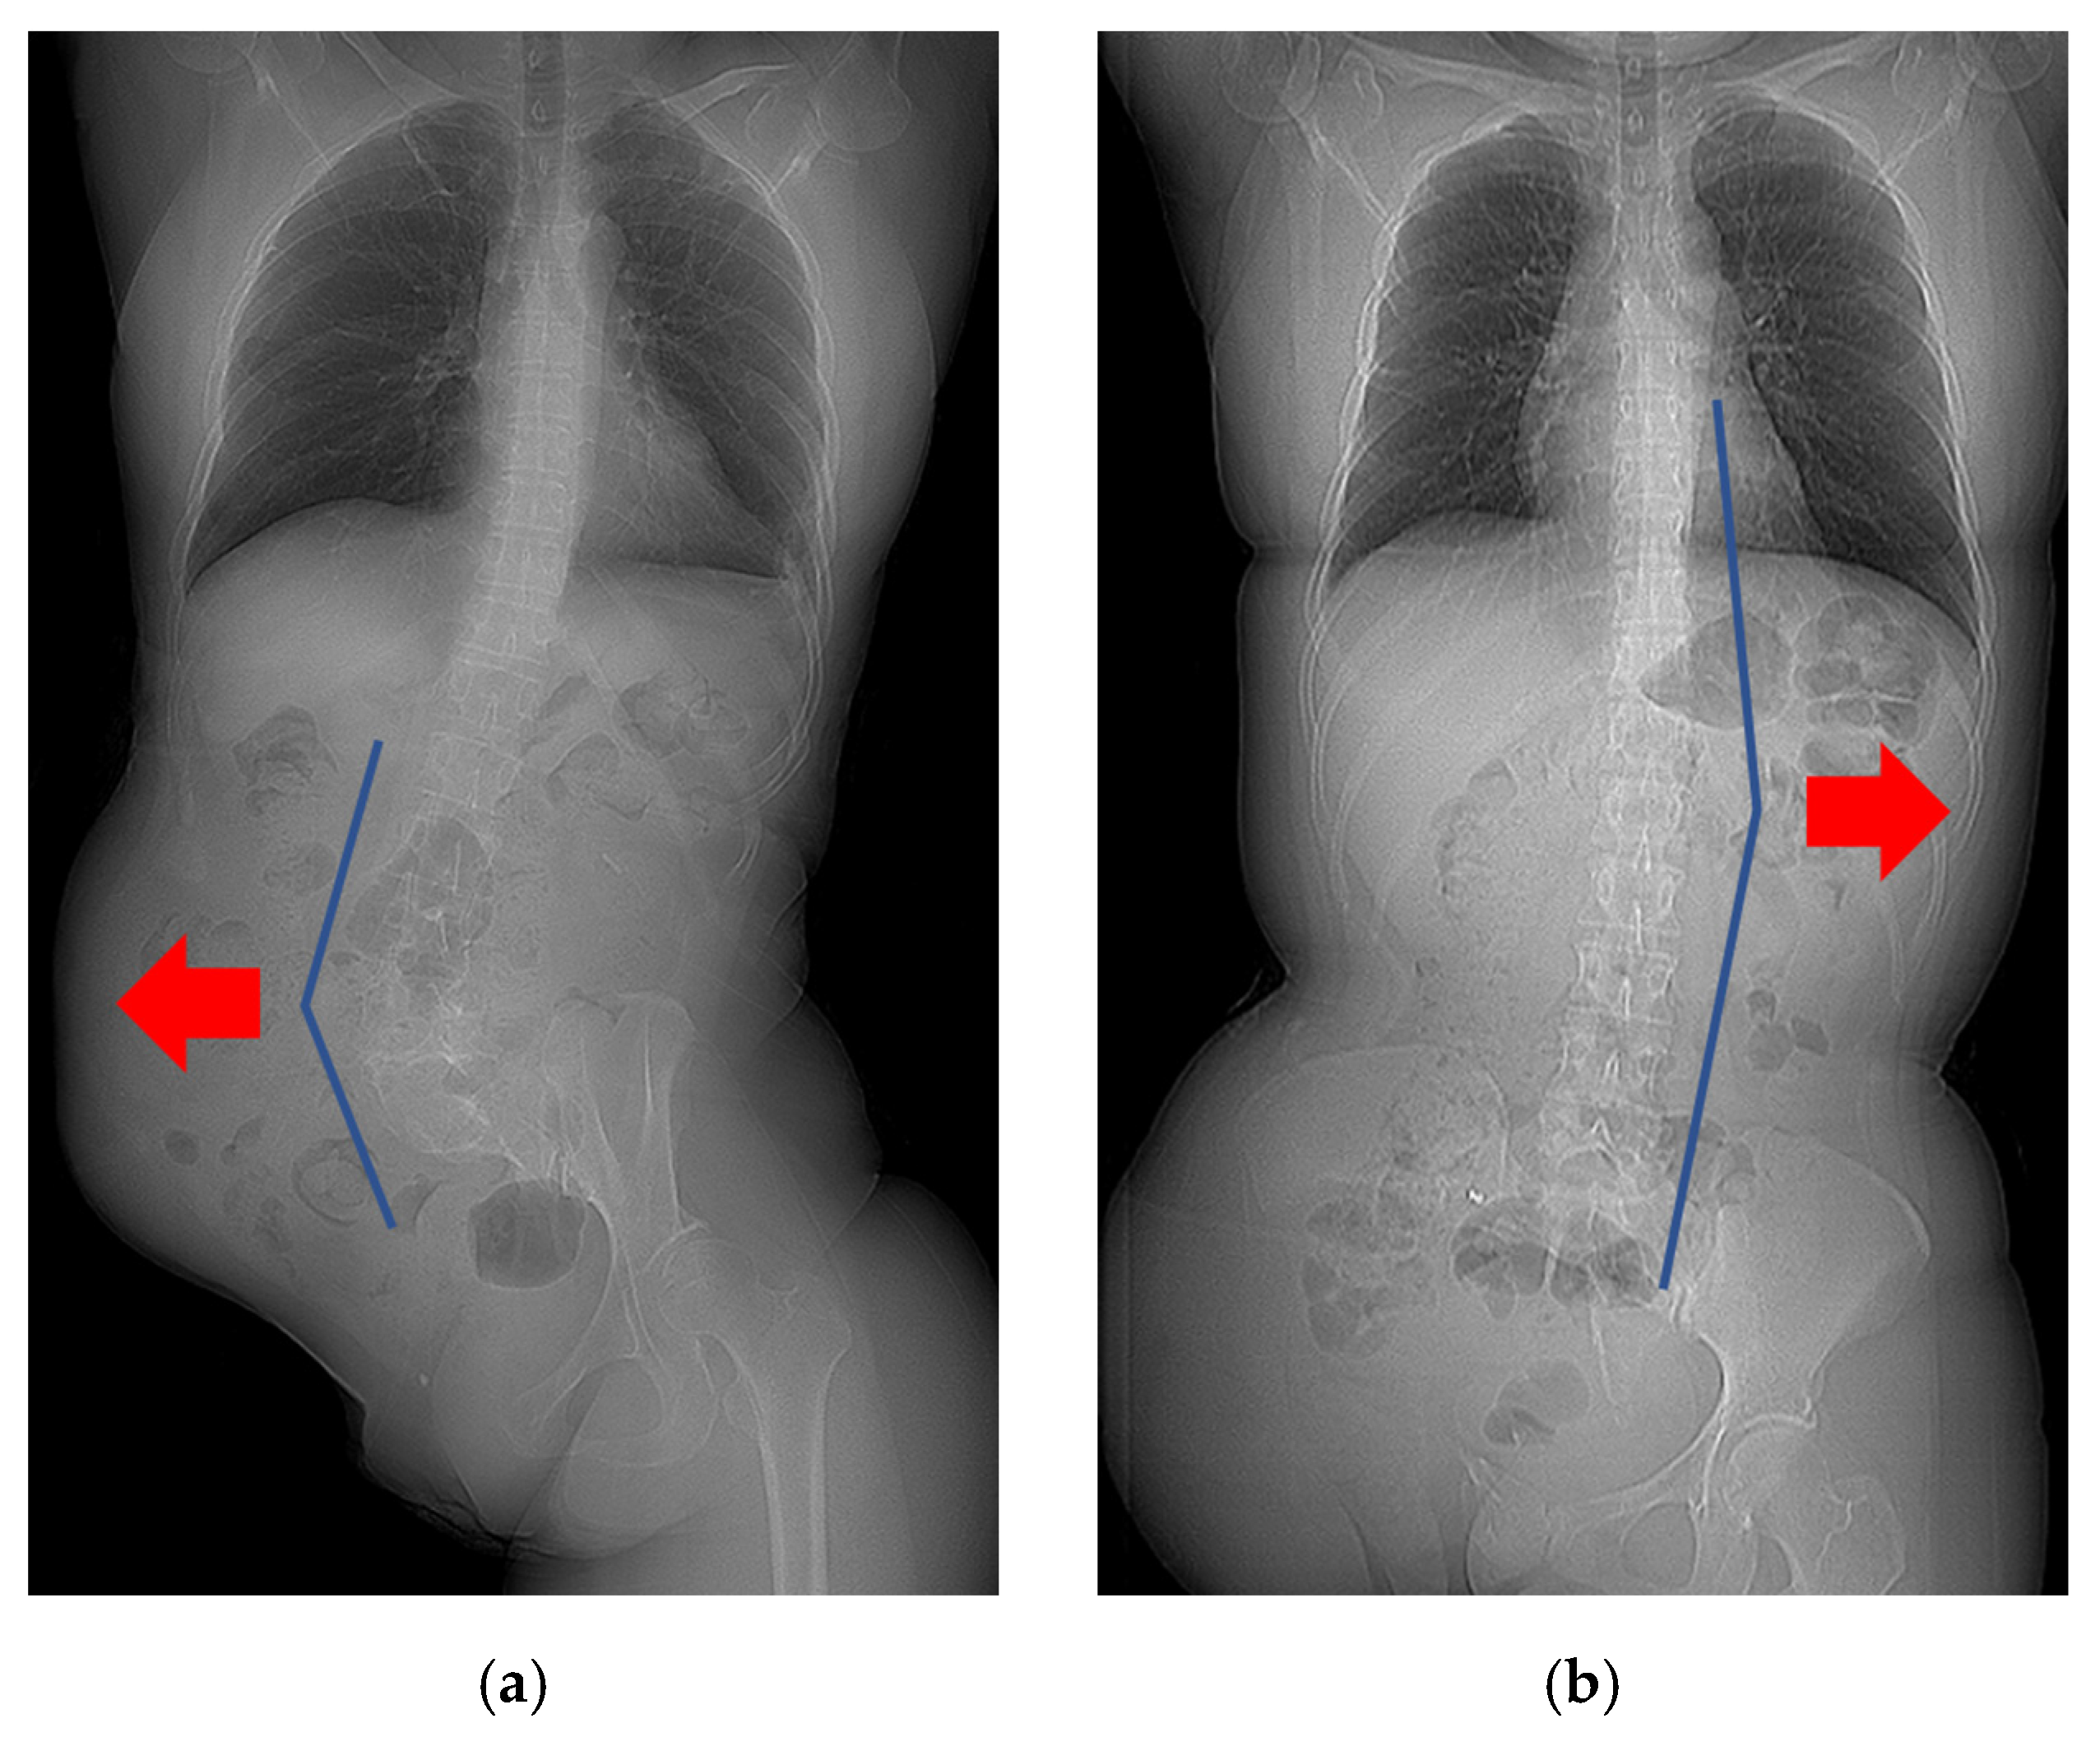

2.2. Parameter Measurements

3.4. Factors That Affected the Curve Direction of Scoliosis